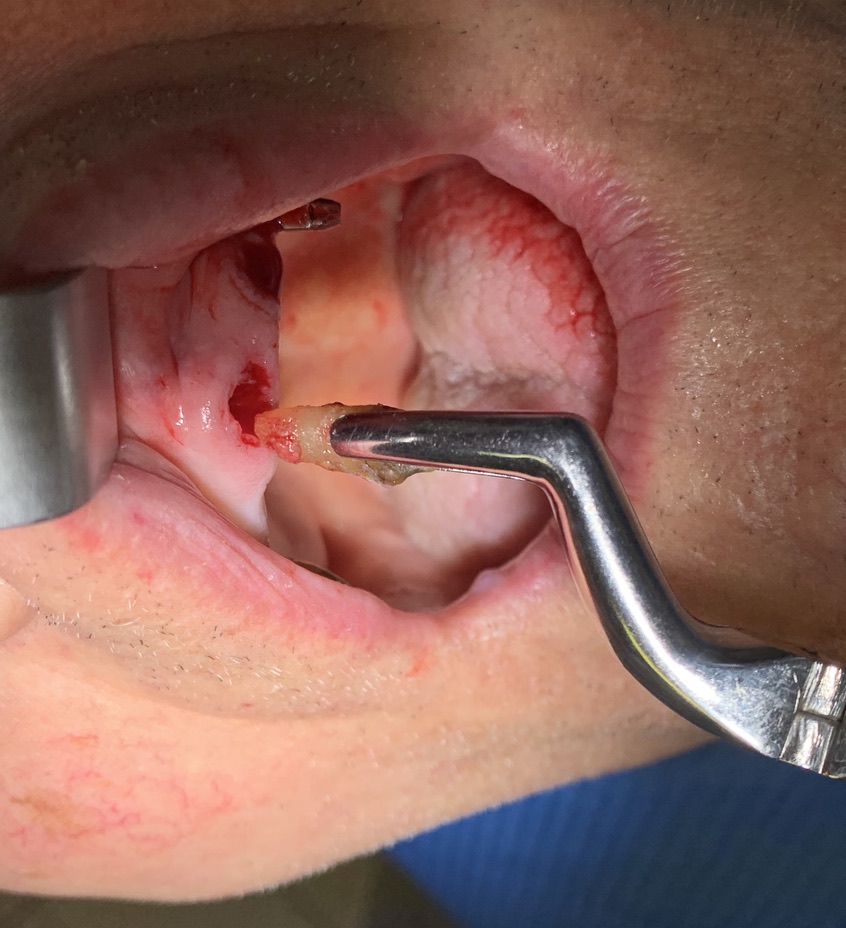

Implant type: Tramonte     No. Implants inserted: 2       Welding: No      Dental area: 21   23

Intraoral Rx app: Vix win       CT scan: No      Extraction situation: immediate post extraction implants        Density according to Misch: D2

D- make the detachment useless,

E- reduce bone consumption to almost zero, for perforation and insertion, F- favour the formation of the gingival collar even in the presence of free gum,